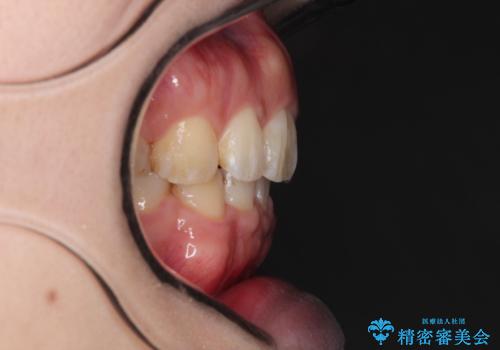

がたがたと出っ歯を直したい ワイヤーによる抜歯矯正

- ガタガタと出っ歯を主訴に来院されました。

上下左右の歯を1本ずつ、合計4本抜歯してワイヤーにて矯正治療をすることとなりました。

前から4番目の歯を抜歯することが多いのですが、右上の前から5番目の歯が神経の治療済みであり、こちらの歯を抜歯する計画としました。

通常より治療期間を要しましたが、健康な歯を残すことができました。